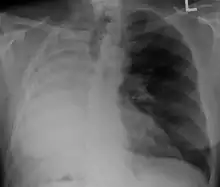

X-ray of a person who has had their right lung removed. Note how fluid has replaced the lung